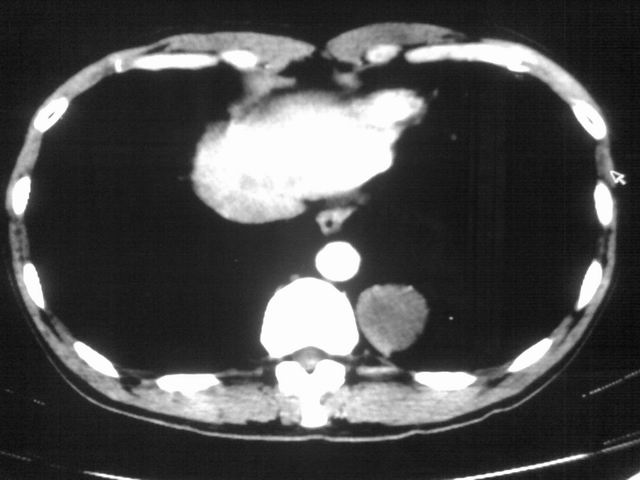

以下是引用苯小孩在2007-4-24 19:46:00的发言:[br]左下肺内侧基底段,见类圆形病灶,边缘清晰光滑.强化后轻中度强化.<平扫第4层面似有从腹主动脉相连血管影,可惜强化扫描这层没有抓住>考虑:左下肺隔离症.建议dsa或薄层强化重建观察.

以下是引用同在2007-4-24 20:11:00的发言:[br]考虑肺隔离症